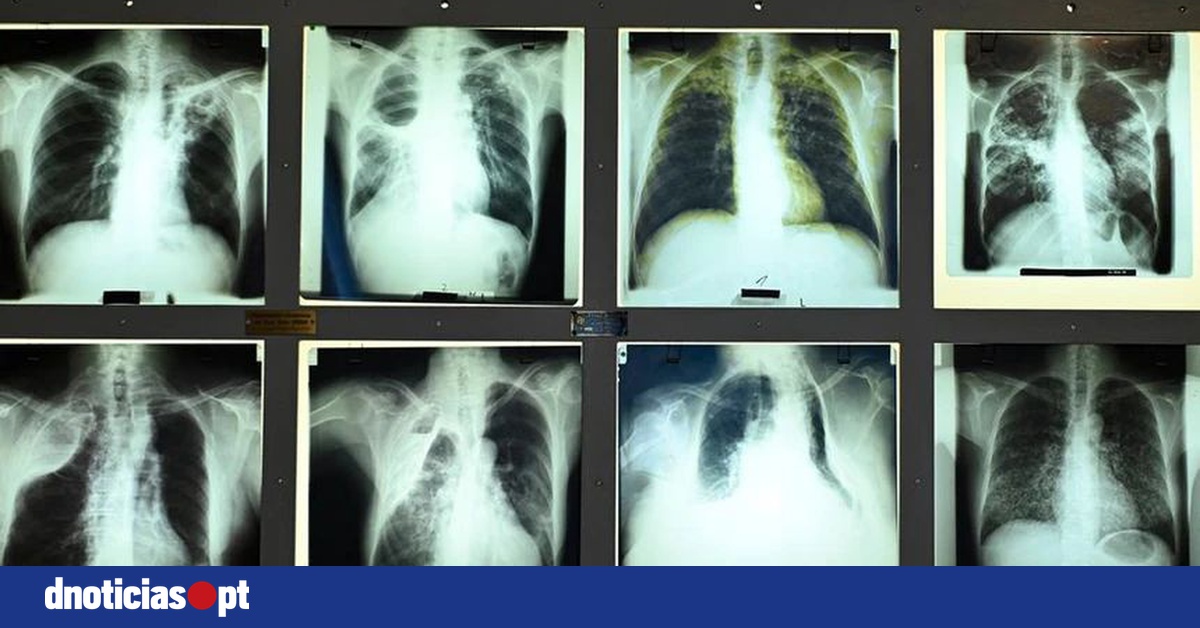

Portugal registou número de casos de tuberculose mais baixo de sempre

Portugal registou 1.536 casos de tuberculose em 2024, o valor mais baixo de sempre, segundo um relatório da Direção-Geral da Saúde, que mostra que entre os imigrantes a taxa é quase três vezes superior à média nacional.

O Relatório de Vigilância e Monitorização da Tuberculose em Portugal, divulgado no Dia Mundial da Tuberculose, confirma a tendência de descida da tuberculose no país, com uma taxa de notificação de 14,3 casos por 100 mil habitantes.